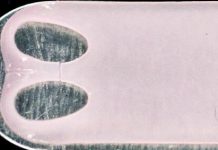

Researchers Create ‘Pill-on-a-String’ Technique to Better Detect Cancer

The unique technique can rub the esophagus and scrape away cells that scientists can then examine for cancer.